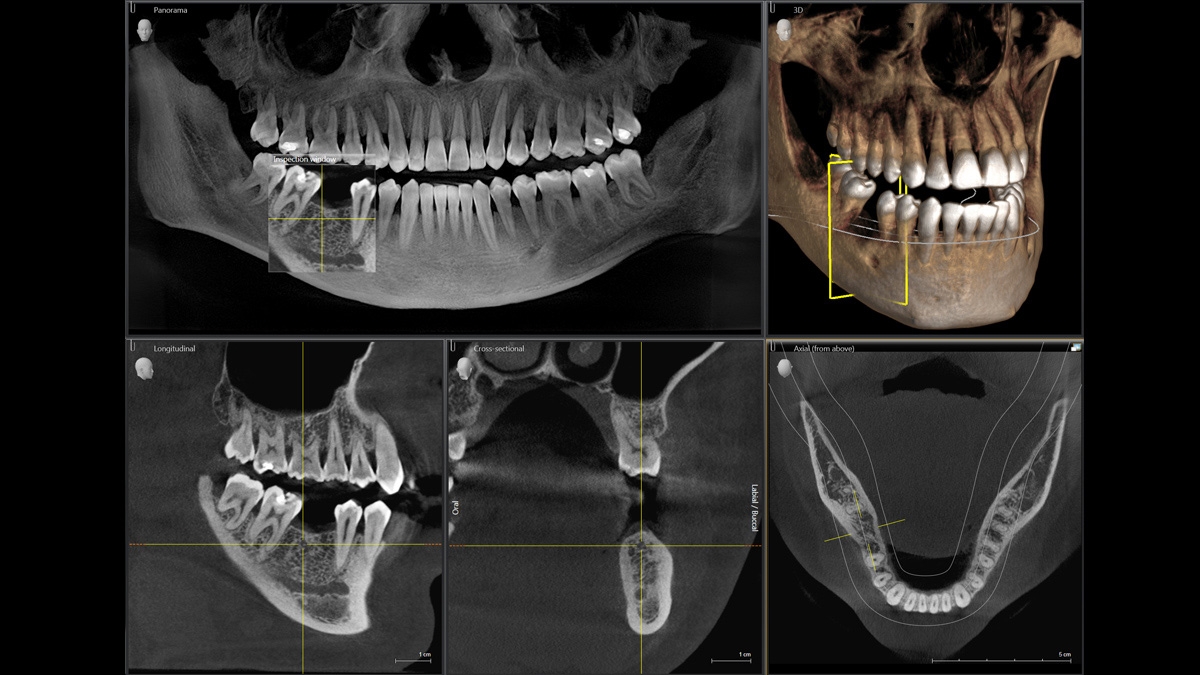

Диагностика последнего поколения, идеально решающая задачи рентгеновского обследования независимо от размеров клиники. Поля изображения зависят от определенной клинической картины, поэтому специалистам так удобно работать с ORTHOPHOS SL 3D. Данная установка делает объёмные картинки для одиночной реставрации в 3D качестве полностью всей челюсти такого размера, которого требуется.

ОБЪЁМ ДЛЯ ЛЮБЫХ ЦЕЛЕЙ

Планирование одиночной реставрации, эндодонтические исследования и пр. – для этого специалист может выбрать объёмные варианты 8 х 8 см или 11 х 10 см, также предлагается объём 5 х 5,5 см. Снимки в HD-качестве, стандартные настройки или выбор объёма обследования в зависимости от диагноза — всё это врач получает в отличном качестве, а для пациента излучение в районе исследования минимально.

С технологией SL можно за один сеанс получить огромное количество снимков. Те из них, где фокусировка наиболее чёткая, автоматически соединяются. В итоге одна процедура — снимки челюсти полностью в самом лучшем качестве. Даже нестандартные случаи не станут помехой в обследовании. К примеру, при ретинированных зубах уже после того, как снимок сделан, нужную область можно выделить подробнее, и в ещё одном рентгене необходимость отпадает.

Программное наполнение для работы с изображениями с модулем MARS*

Металлические элементы в ротовой полости могут привести к возникновению помех на снимке. Благодаря наличию программного обеспечения MARS наличие объектов из металла определяется автоматически, влияние артефактов нивелируется. Таким образом не требуется повторного изображения для уточнения диагноза.